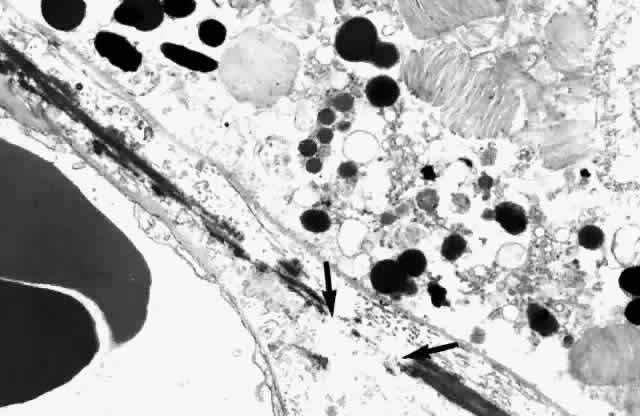

and subcapillary zone of the choriocapillaris (Fig. 10). The elastic tissue and collagenous layers of Bruch's membrane become

circularly oriented around the edge of the optic nerve.  Fig. 10. Passageway between elastic fibers (between arrows). (× 12,900) Fig. 10. Passageway between elastic fibers (between arrows). (× 12,900)